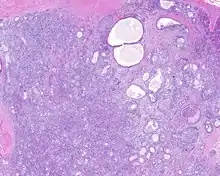

Sclerosing polycystic adenosis (also abbreviated SPA) is a rare salivary gland tumor first described in 1996 by Dr. Brion Smith.[1] The major salivary glands, specifically the parotid gland (about 70% of cases) and the submandibular gland, are affected most commonly.[2][3] Patients usually come to clinical attention with a mass or swelling in their salivary glands in the 5th decade of life, with females affected much more commonly than males.[1][2] Nearly all of the cases reported so far have a benign behavior (no recurrence and no metastasis), although there is a single case that has had an associated malignant transformation (becoming an invasive cancer).[4]

When reviewed by a pathologist, the findings are quite similar to fibrocystic changes of the breast, although they are different enough, that it is now recognized to actually represent a true neoplasm (clonal proliferation) through various studies.[5] Specifically, the lesions are usually well-circumscribed, containing lobules of haphazardly arranged ducts, myoepithelial cells, and acini that have abundant sclerosing or hyalinized fibrosis. Apocrine change is quite common in the ductal cells.[6] The ducts range from small ductules to cystically dilated spaces (more than 4 striated duct-widths across), often containing products of secretion or reactive histiocytes. A very curious and characteristic finding in all of the lesions is the presence of bright pink (eosinophilic) acinar granules (which are altered zymogen).